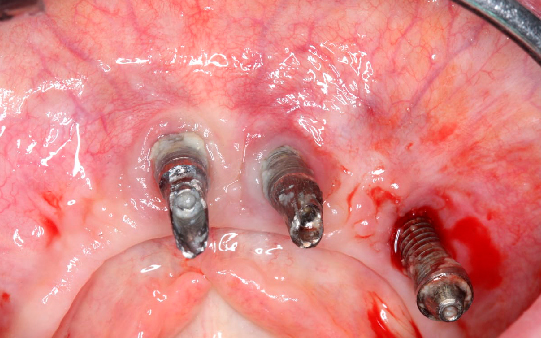

Protocolo em Resina Acrílica: boa estética, acessível, indicado para reabilitações com ótimo custo-benefício.